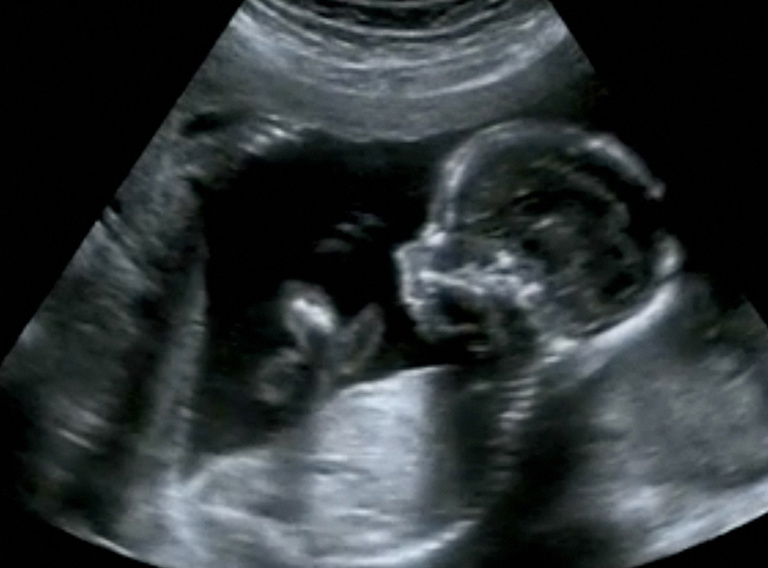

In vitale organen van ongeboren baby’s zijn er al sporen van luchtvervuiling terug te vinden. Dat blijkt uit nieuw onderzoek van Universiteit Hasselt en de Universiteit van Aberdeen, dat gepubliceerd werd in The Lancet Planetary Health. “Eerder onderzoek van ons team toonde al aan dat er in alle trimesters van de zwangerschap roetdeeltjes in de placenta terug te vinden zijn. Nu zien we dat die roetdeeltjes daar niet blijven, maar ook echt in de organen van de foetus terecht komen”, zegt prof. dr. Tim Nawrot (UHasselt).

Het is voor het eerst dat een team van wetenschappers roetdeeltjes kan detecteren in de organen van foetussen. “Dankzij de vele stalen die we ter beschikking hebben via ons geboortecohort in samenwerking met Ziekenhuis Oost Limburg in Genk, konden we eerder al ontdekken dat blootstelling aan luchtvervuiling bij zwangere vrouwen ervoor kan zorgen dat minuscule roetdeeltjes in de placenta terecht komen, nu wilden we nagaan welke impact die roetvervuiling precies kan hebben op de ontwikkeling van de foetus in de baarmoeder”, zegt prof. Tim Nawrot. “We zien nu voor het eerst dat roetdeeltjes een weg vinden tot in de organen van de foetus, waaronder de lever, de longen en zelfs de hersenen. En dat terwijl deze organen bij de ongeboren baby nog in volle ontwikkeling zijn.”

“Vooral het feit dat deze roetdeeltjes in de nog volop ontwikkelende hersenen terecht komen, is onrustwekkend”, zegt prof. dr. Paul Fowler van de Universiteit van Aberdeen, die meewerkte aan dit onderzoek. “Dit betekent dat deze nanopartikels via de hersenen in contact komen met het volledig netwerk van cellen en organen in het lichaam van de foetus en hierop kunnen inwerken.”